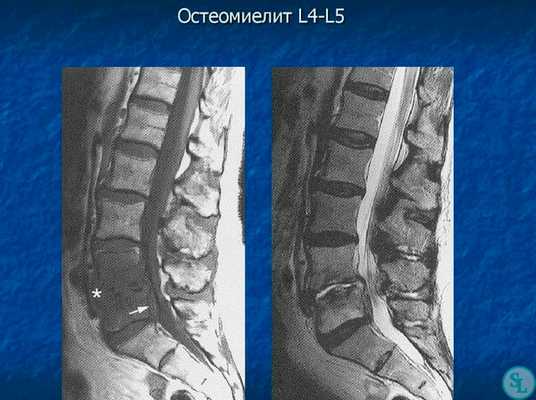

В диагностике заболеваний позвоночника большей популярностью пользуется магнитно-резонансная томография (или точнее «ядерно-магнитно-резонансная»), более безопасная и чувствительная, чем жесткое рентгеновское излучение. На снимках костные структуры получаются черными, но мягкие ткани, наполненные водой, передают все оттенки серого и белого цветов. Это позволяет обнаруживать мельчайшие объекты (узелковые образования, инфильтрации) и отслеживать динамику развития абсцесса.

- МРТ позвоночника. Определяется снижение интенсивности сигнала на Т1-взвешенных снимках и его повышение на Т2-взвешенных изображениях, деформация межпозвоночных дисков, структурные изменения тел позвонков. Чувствительность магнитно-резонансной томографии достигает 96%, точность - 94%, поэтому ее считают «золотым стандартом» диагностики.

Исследование мягких тканей позвоночника с помощью рентгенографии дает неоднозначные результаты: явственно различить нарушения целостности межпозвоночных дисков не удается. Гнойное расплавление и формирование абсцессов можно определить только по размыванию контуров замыкательных пластинок и искажению очертаний тел позвонков.